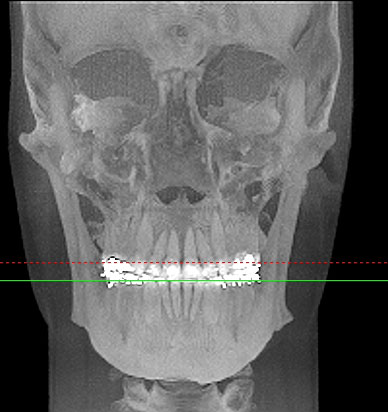

Im folgendem sehen Sie die Darstellung eines Teils des menschlichen Schädels mit Lokalisation des Nervkanales.

Frontalansicht |